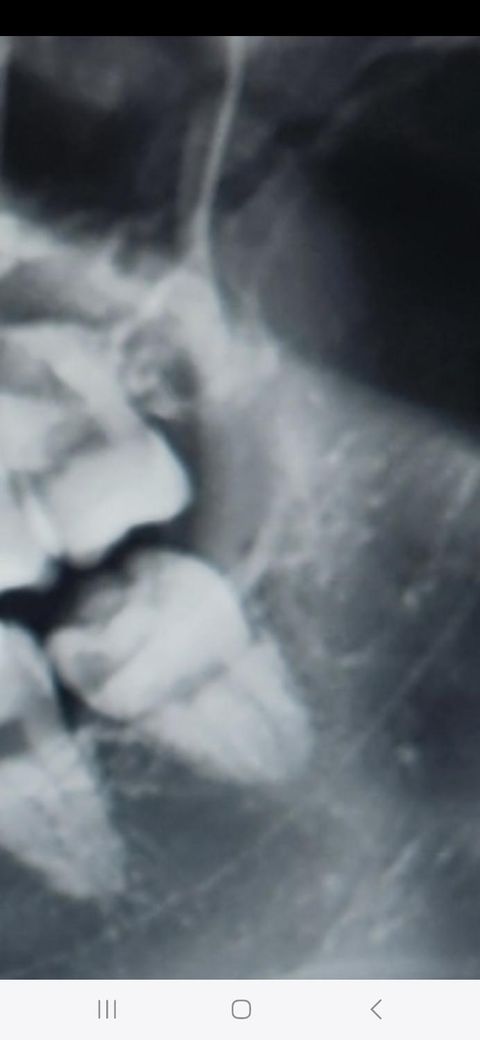

제가 내일 사랑니 예약인데요

두개정도 뽑을것 같긴하네요

매복은 아닌것 같아요